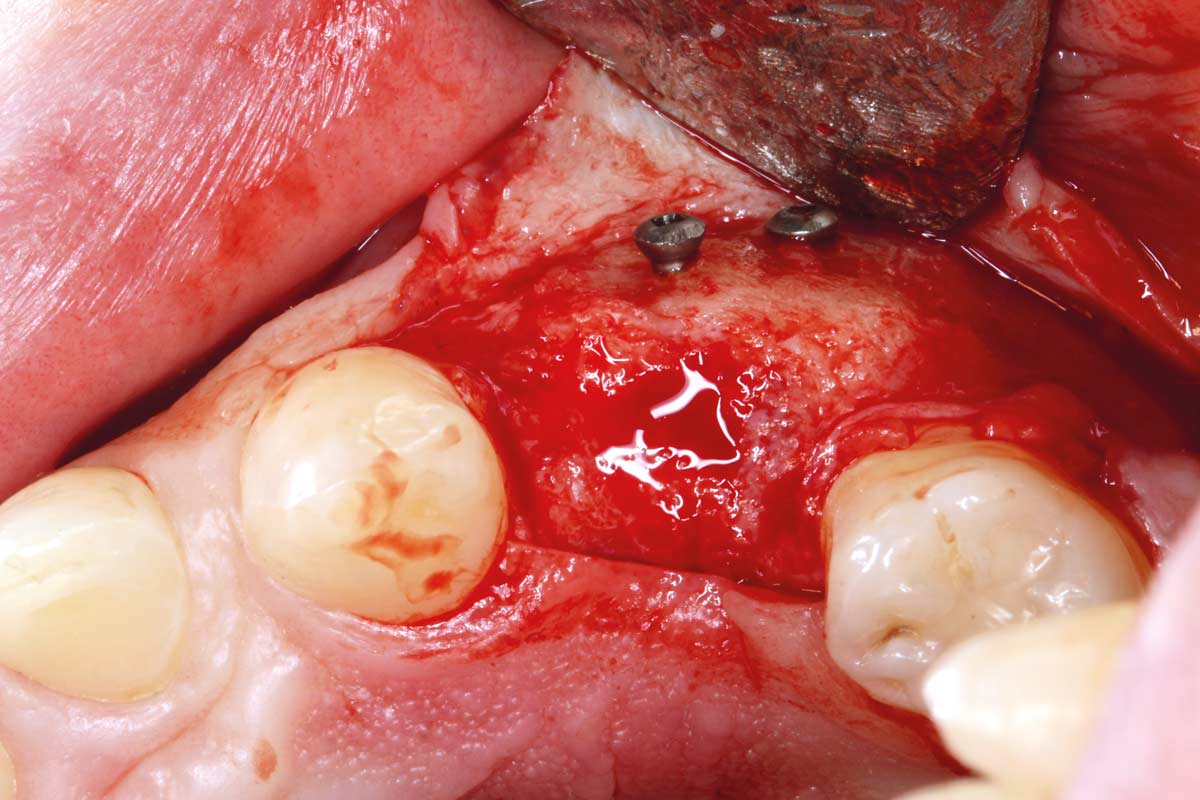

Full-thickness flap preparation bucally and lingually